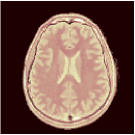

Ground truth (T1, T2, PD) anatomical maps acquired by the MAGIC gold standard [21]

T1 (sec) T1 error T2 (sec) T2 error PD (a.u.) PD error

Table 1 and Figure 2 compare the performances of the MRF baselines against our proposed PGD-Net using and 5 recurrent iterations. We also include inference results using the proposed encoder alone , without proximal iterations. Reconstruction performances were measured by the Normalised RMSE , MAE , Structural Similarity Index Metric (SSIM) [28], the required storage for the MRF dictionary (in DM methods) or the networks, and the algorithm runtimes averaged over the test image slices.

The non-iterative FGM results in incorrect maps due to the severe under-sampling artefacts. The model-based BLIP iterations improve this, however, due to lacking spatial regularisation, BLIP has limited accuracy and cannot fully remove aliasing artefacts (e.g. see T2 maps in Figure 2) despite 20 iterations and very long runtime. In contrast, all deep learning methods outperform BLIP not only in accuracy but also in having 2 to 3 orders of magnitude faster reconstruction times—an important advantage of the learning-based methods. The proposed PGD-Net consistently outperforms all baselines, including DM and learning-based methods, over all defined accuracy metrics. This is achieved due to learning an effective spatiotemporal model (only) for the proximal operator i.e. the and Bloch networks, directly incorporating the physical acquisition model H into the recurrent iterations to avoid over-parameterisation of the overall inference model, as well as enforcing reconstructions to be consistent with the Bloch dynamics and the k-space data through the multi-term training loss (6). The MRFCNN and SCQ over-parametrise the inference by 1 and 3 orders of magnitude larger model sizes (the SCQ requires larger memory than DM) and are unable to achieve PGD-Net’s accuracy e.g. see the corresponding over-smoothed T2 maps in Fig. 2. Finally, we observe that despite having roughly the same model size (storage), the encoder alone predictions are not as accurate as the results of the PGD-Net’s recurrent iterations. By increasing the number of iterations we observe that the PGD-Net’s accuracy consistently improves despite having an acceptable longer inference time.